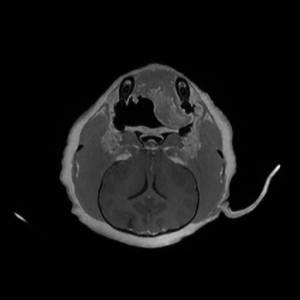

Main Gallery

Playing with a photo gallery function. It is possible to have multiple galleries, each within a namespace.